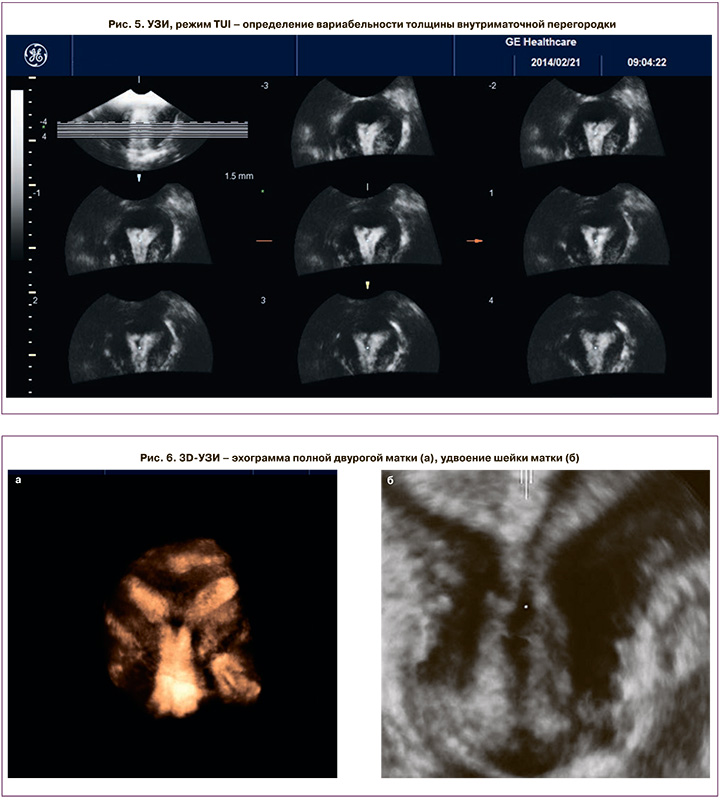

Трехмерными критериями полной внутриматочной перегородки (класс U2b) стали: интактный НКМ, V/Y-образная форма полости, сформированная внутриполостной структурой, разделяющей ее на две гемиполости, доходящая до внутреннего зева шейки матки. В ФС мы могли оценить симметричность обеих гемиполостей и объем каждой из них, что может быть решающей информацией перед выполнением вспомогательных репродуктивных технологий и переноса эмбриона. Режим TUI позволил более четко определить вариабельность толщины перегородки (рис. 5), которая в нашем исследовании составила максимально от 15 до 27 мм и минимально от 0,3 до 2,2 мм. При проведении 3D-ГСГ катетер устанавливался в проекции внутреннего зева шейки матки для адекватной параллельной инсуффляции обеих гемиполостей, при невозможности – катетер попеременно вводился в каждую гемиполость. У 43% обследованных с отягощенным акушерско-гинекологическим анамнезом или отсутствием (выраженным оскудением) кровотока перегородки мы произвели ее резекцию биполярной петлей с обязательным введением противоспаечного барьера и назначением комбинированных оральных контрацептивов на 3–6 месяцев, у 22% из них в течение последующих 2 лет беременность закончилась самопроизвольными срочными родами.